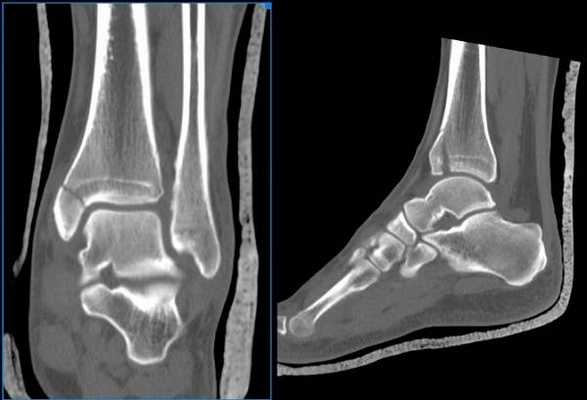

МРТ или КТ суставов, что лучше?

В отношении строения костных и хрящевых элементов сустава большей информативностью обладает компьютерная томография. Метод основан на применении ионизирующего излучения. В результате КТ получают послойные изображения. Снимки детально отражают состояние твердых структур, которые обладают высокой поглощающей способностью. Данный вид рентгенологического исследования актуален при подозрении на переломы, трещины, патологические состояния костей и хрящей сустава.

Недостатками КТ являются лучевая нагрузка и слабая визуализация состояния мягких тканей. Для повышения информативности сканирования применяют контрастное усиление с помощью инъекции йодсодержащего раствора.

Компьютерная томография голеностопного сустава

КТ или МРТ коленного сустава, что лучше?

Благодаря КТ можно досконально исследовать состояние костей, но МРТ дает значительно лучшие изображения мягких тканей. Поэтому снимки, полученные с помощью КТ, не могут предоставить такой точной информации о состоянии хрящевой ткани и других мягкотканных структур, что дает МРТ коленного сустава. Но именно компьютерная томография применяется, если в теле больного установлены металлические протезы, так как рентгеновское излучение не может спровоцировать их смещение.